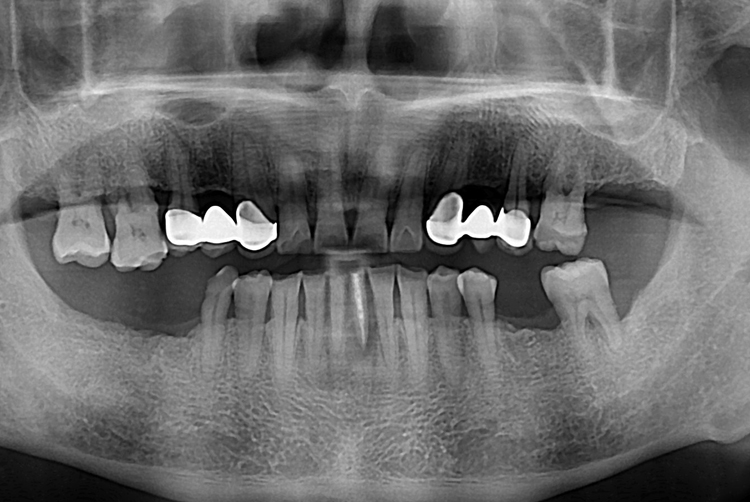

[임플란트] 앞니 임플란트

치료전 : 2019-08-16

치료후 : 2019-10-30

세종치과는 많은 환자와 다양한 케이스를 바탕으로

항상 편안한 임플란트 수술을 제공하고자 노력하고,

오래동안 튼튼히 쓸 수 있는 임플란트 수술을 가장 큰 목표로 삼고 있습니다.